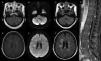

Brain and spine MRI. (A, D) Axial T1-weighted contrast-enhanced MRI shows multiple infra and supratentorial ring-enhancing lesions that were hyperintense on the (B, E) diffusion-weighted image (DWI) sequence with perilesional edema seen on the (C, F) fluid-attenuated inversion recovery (FLAIR) sequence. (G) Coronal T1-weighted contrast-enhanced MRI of the spine shows a contrast-enhancing lesion of the central spinal cord.

Routine blood workup was relevant for an elevated C-reactive protein in 1.68mg/dL (range: 0–1), the rest of the workup, including a full blood count, serum electrolytes, renal and liver function tests were within normal ranges. Serum testing for syphilis, hepatitis C and HIV were negative. Magnetic resonance imaging (MRI) of the brain showed multiple infra and supratentorial abscesses in different stages (Fig. 1A–F). The cerebrospinal fluid analysis (CSF) showed elevated proteins in 121mg/dL (range: 10–45), pleocytosis with 30cells/mm3 (range: 0–10) of which 70% were polymorphonuclear a normal glucose (60mg/dL [range: 50–80]) and CSF/serum glucose ratio (0.7), with negative Gram and acid-fast bacilli stains as well as polymerase chain reaction (PCR) testing for Toxoplasma gondii, nucleic acid amplification for Mycobacterium tuberculosis, and serum cryptococcal antigen. With those results, we started treatment with ceftriaxone, vancomycin, and metronidazole. To determine the abscesses source, we performed a dental exam and a transesophageal echocardiogram with unremarkable results; lastly, a whole-body computed tomography (CT) revealed multiple liver abscesses.

Three days after admission, she developed acute urinary retention, and an MRI of the spine revealed a central spinal cord abscess at the twelfth thoracic vertebra (Fig. 1G). On day eight, a rapidly-growing mycobacterium (RGM), typified as Mycobacterium mucogenicum by PCR amplification with the GenoType Mycobacterium AS (additional species) probe assay (Hain Lifescience, GmbH, Nehren, Germany) resistant to levofloxacin and susceptible to amikacin, trimethoprim/sulfamethoxazole, azithromycin, clarithromycin, moxifloxacin, and linezolid was isolated from the CSF. We adjusted treatment to IV amikacin, linezolid, and azithromycin for four weeks. Neurological symptoms gradually improved. After excluding primary immune deficiencies, we discharged her five weeks after admission on oral azithromycin, moxifloxacin, and trimethoprim/sulfamethoxazole. Six months after discharge, neurological symptoms resolved as well as the MRI lesions leading to stopping antibiotics. On follow-up one year after being diagnosed, the patient remains asymptomatic.